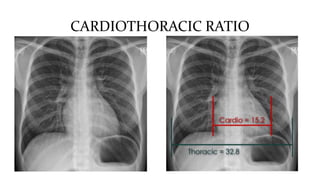

This document discusses key aspects of thorax radiology including positioning for PA and AP views, assessing heart size, visibility of anatomical structures like the scapulae, lungs zones, and measurements like cardiothoracic ratio. It provides guidance on evaluating rotation, inspiration, and penetration on chest x-rays as well as identifying structures like the lobe of azygos vein and aortic knuckle.